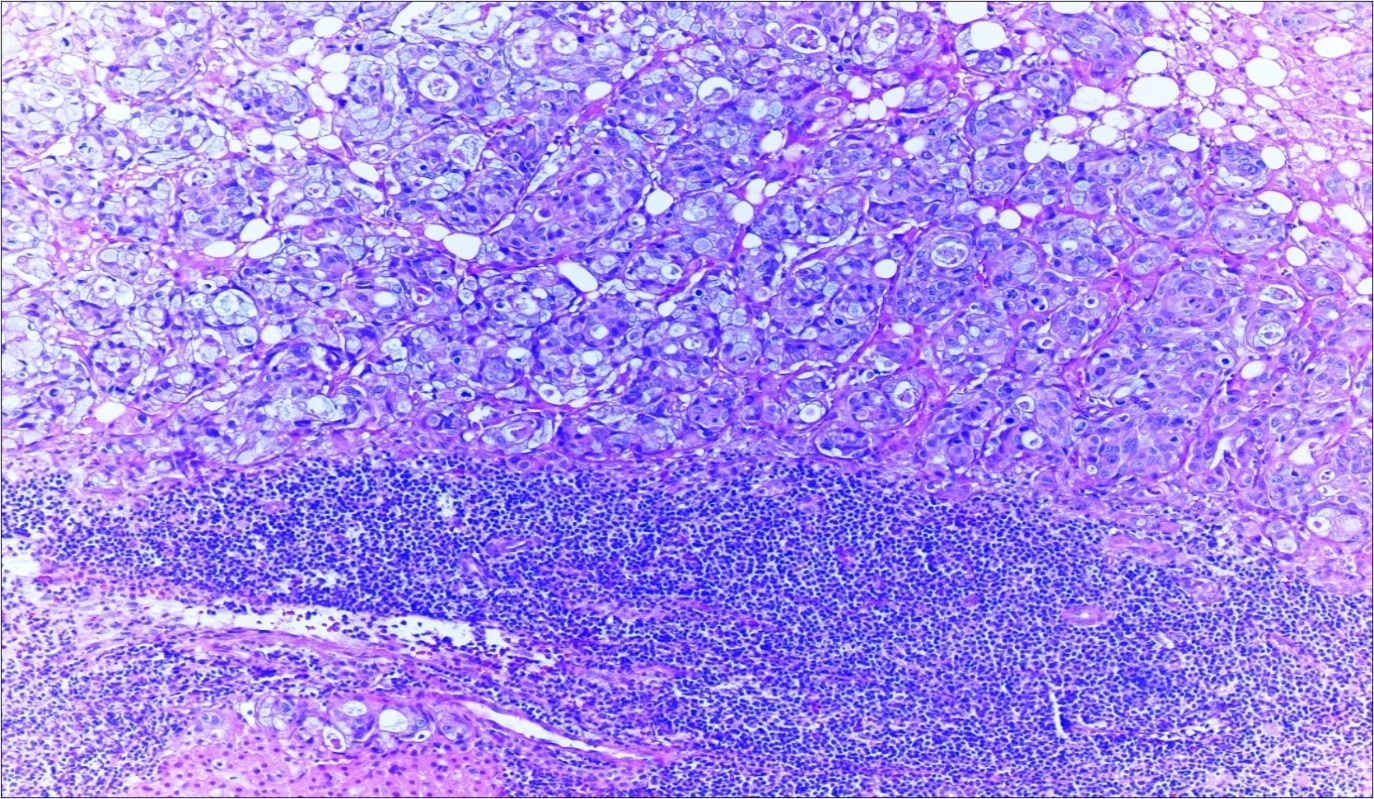

A 63-year-old woman presented to the Department of General Surgery as an outpatient with abdominal pain. Physical examination showed the signs of acute appendicitis and appendectomy was performed. During microscopic examination, a small focus of atypical monotonous lymphoid cell population was seen and the material was sampled totally. The pathological examination revealed MALT lymphoma (Figure 1), with diffuse positivity of cluster of differentiation (CD) 20 (Figure 2), CD 79a and B-cell lymphoma (Bcl- 2) (Figure 3) with just a few CD3 positive lymphoid cells. However, no evidence of adenocarcinoma was found in the appendectomy specimen. After the diagnosis of lymphoma, a complete colonoscopy was planned and this revealed a solid tumoral mass in the caecum measuring 5x4x4 cm. Computed tomography of the abdomen and pelvis revealed mesenteric lymphadenopathy associated with a mass in the caecum with multiple nodules in liver consistent with metastasis (Figure 4). Frozen sections were not obtained since the treatment method would not be affected. The patient underwent anterior resection with regional lymphadenectomy, with the pathological assessment of the resected specimen revealing a collision tumor consisting of a poorly differentiated adenocarcinoma extending through the muscularis propria with MALT lymphoma (Figure 5). Microscopic evaluation of the 11 regional lymph nodes in the mesentery of the resected colon and liver biopsy showed diffuse infiltration of MALT lymphoma with metastasis of adenocarcinoma (Figure 6). According to immunohistochemistry, atypical lymphocytes were positive for CD 20, Bcl-2, and negative for CD3, CD5, CD10, CD23, Bcl-6, terminal deoxynucleotidyl transferase, and cyclin D1. The proliferation fraction (MIB-1 immunostaining) was approximately 20%. The morphological and immunohistochemical findings were used to confirm the diagnosis of synchronous presentation of MALT lymphoma and colon adenocarcinoma within the caecum, mesenteric lymph nodes and liver metastases.

Figure 4.Adenocarcinoma with MALT lymphoma infiltration of liver (h&e;200)

Figure 5.Adenocarcinoma with MALT lymphoma infiltration of colon (h&e;200)

Figure 6.Adenocarcinoma with MALT lymphoma infiltration of lymph node (h&e;200)